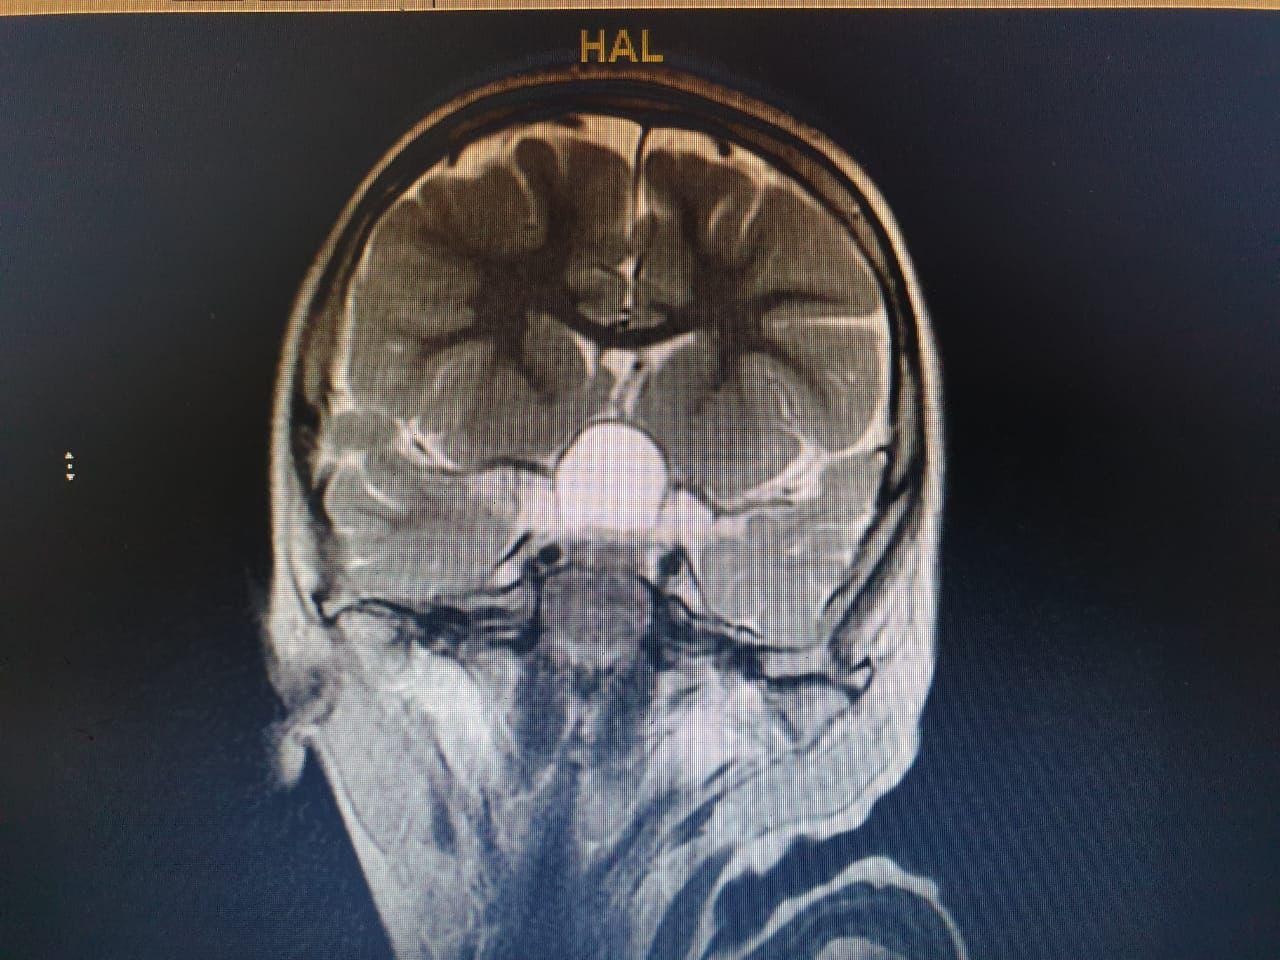

وعلى الفور أجرى الفريق فحوصات متقدمة ، واتضح وجود"ورم" بقاع الجمجمة ، ومتصل بالغدة النخامية.

وأشار المتحدث الرسمي بصحة الطائف سراج الحميدان ,أن الفريق الجراحي للمخ والأعصاب ، تدخل جراحيا بعملية استمرت 7 ساعات لإزالة الورم بالرغم من خطورة الوضع ، وتكللت بالنجاح بفضل الله .